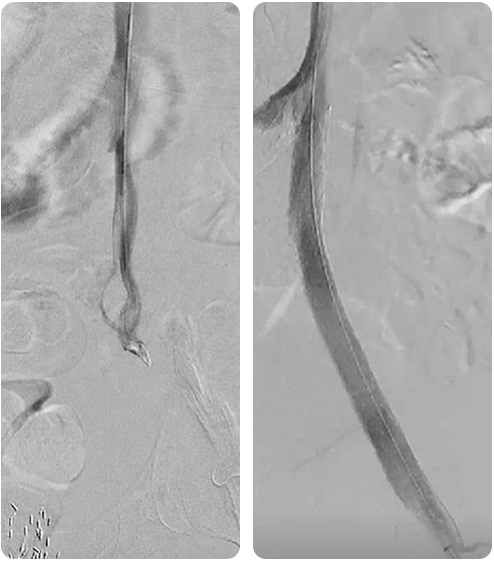

Successful Revascularization of a 99% Left CFA Stenosis Via a Radial Approach Facilitated by the Sublime™ Microcatheter

Amit Srivastava, MD

A man in his early 70s with a prior medical history of a left femoral endarterectomy, peripheral artery disease, diabetes, hyperlipidemia, and hypertension presented with a recurrent wound in his left lateral malleolus from the original femoral endarterectomy. An arterial ultrasound demonstrated severe left femoral arterial stenosis with peak systolic velocity at 300 cm/second. Based on the patient’s arterial ultrasound and prior history, the patient was immediately taken to the angiography suite.